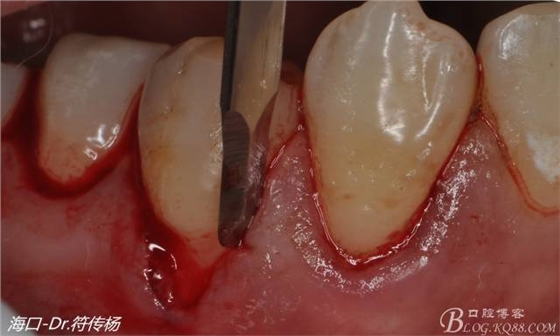

手術(shù)步驟:

首先用顯微手術(shù)刀切斷手術(shù)范圍內(nèi)的牙周韌帶

然后使用下頜開隧刀剝離牙齦

最后使用牙齦乳頭分離器分離牙齦乳頭